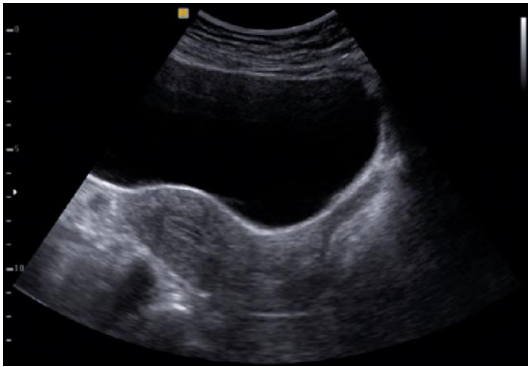

Analise a imagem ultrassonográfica a seguir.

A via de realização dessa ultrassonografia e a fase do ciclo menstrual na qual se encontra o útero são, respectivamente,